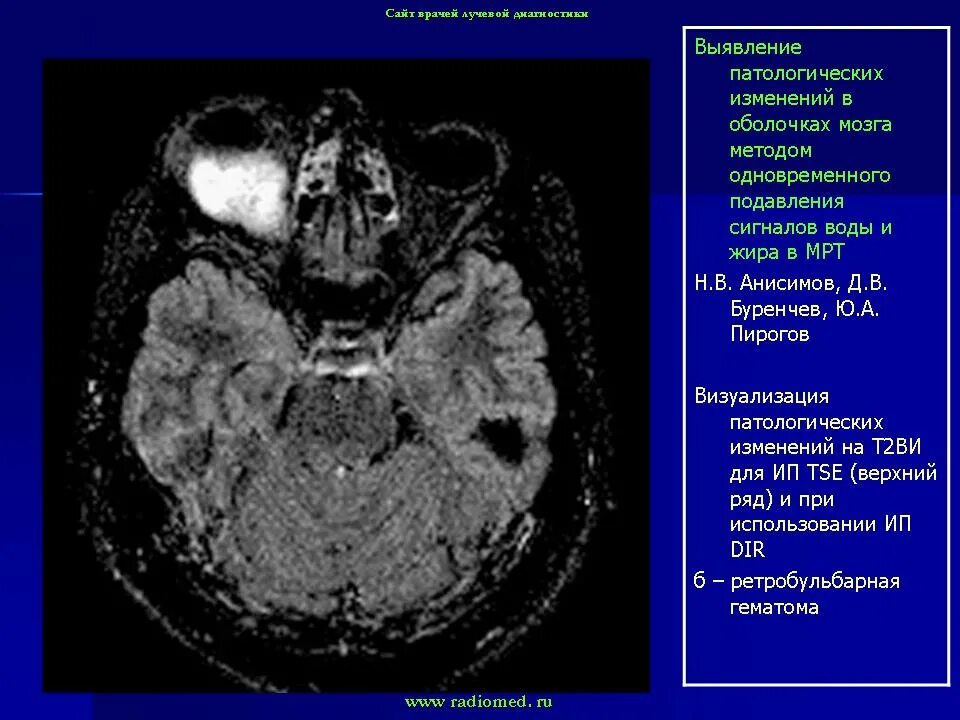

Данные кт